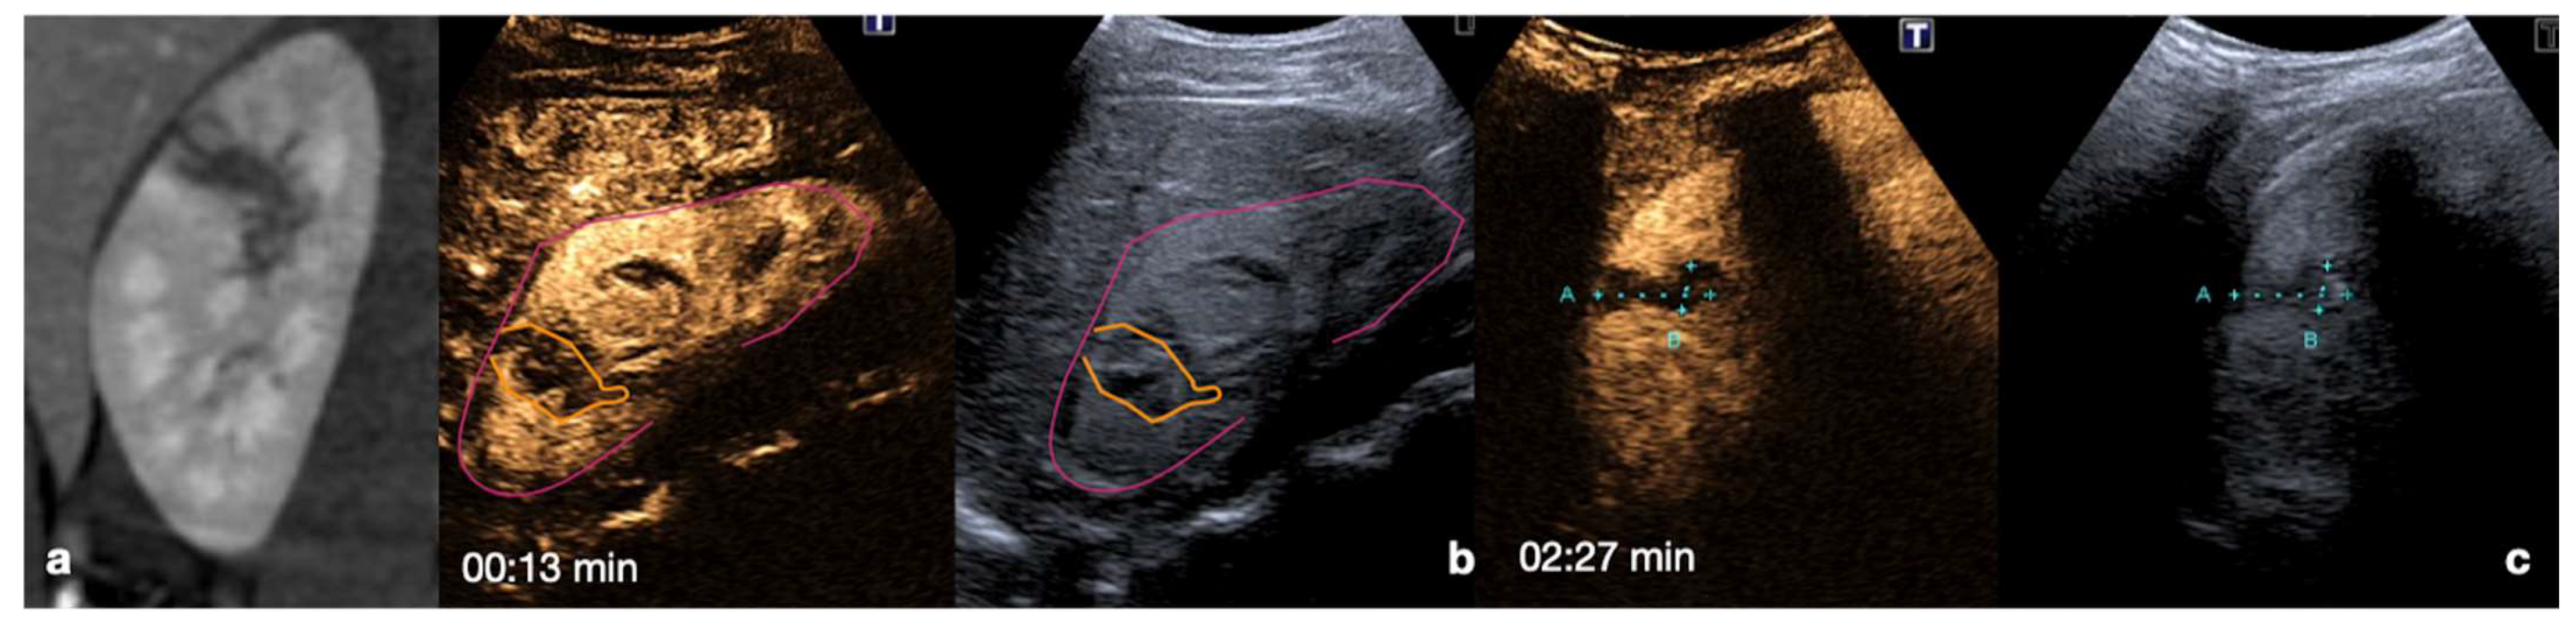

4.1. Step 1

4.2. Step 2

4.3. Step 3

4.4. Step 4

4.5. Step 5